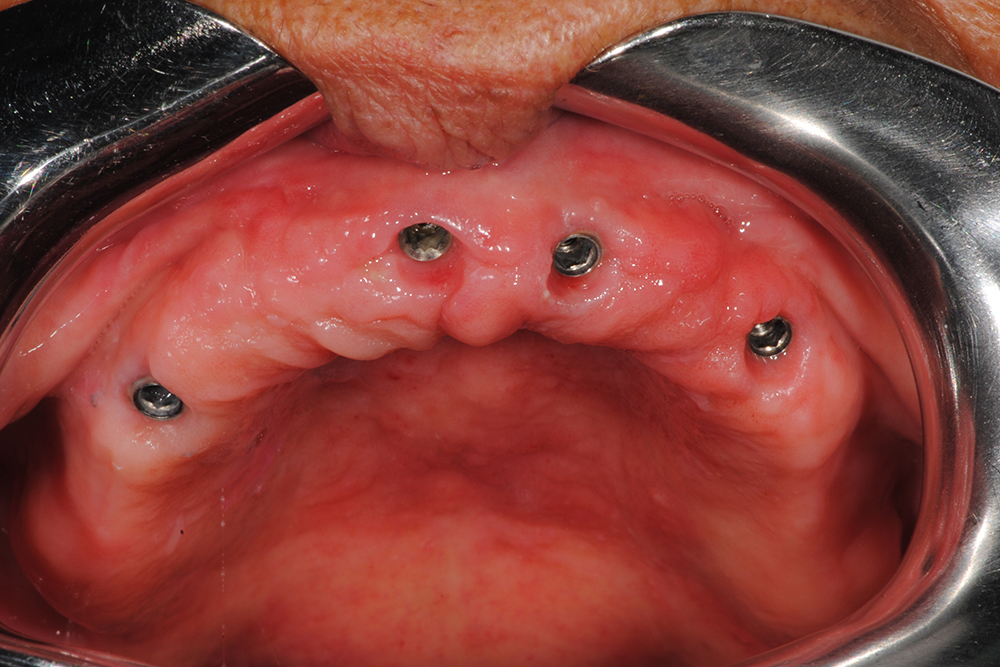

Ripristino dell’arcata superiore ed inferiore su overdenture su barra